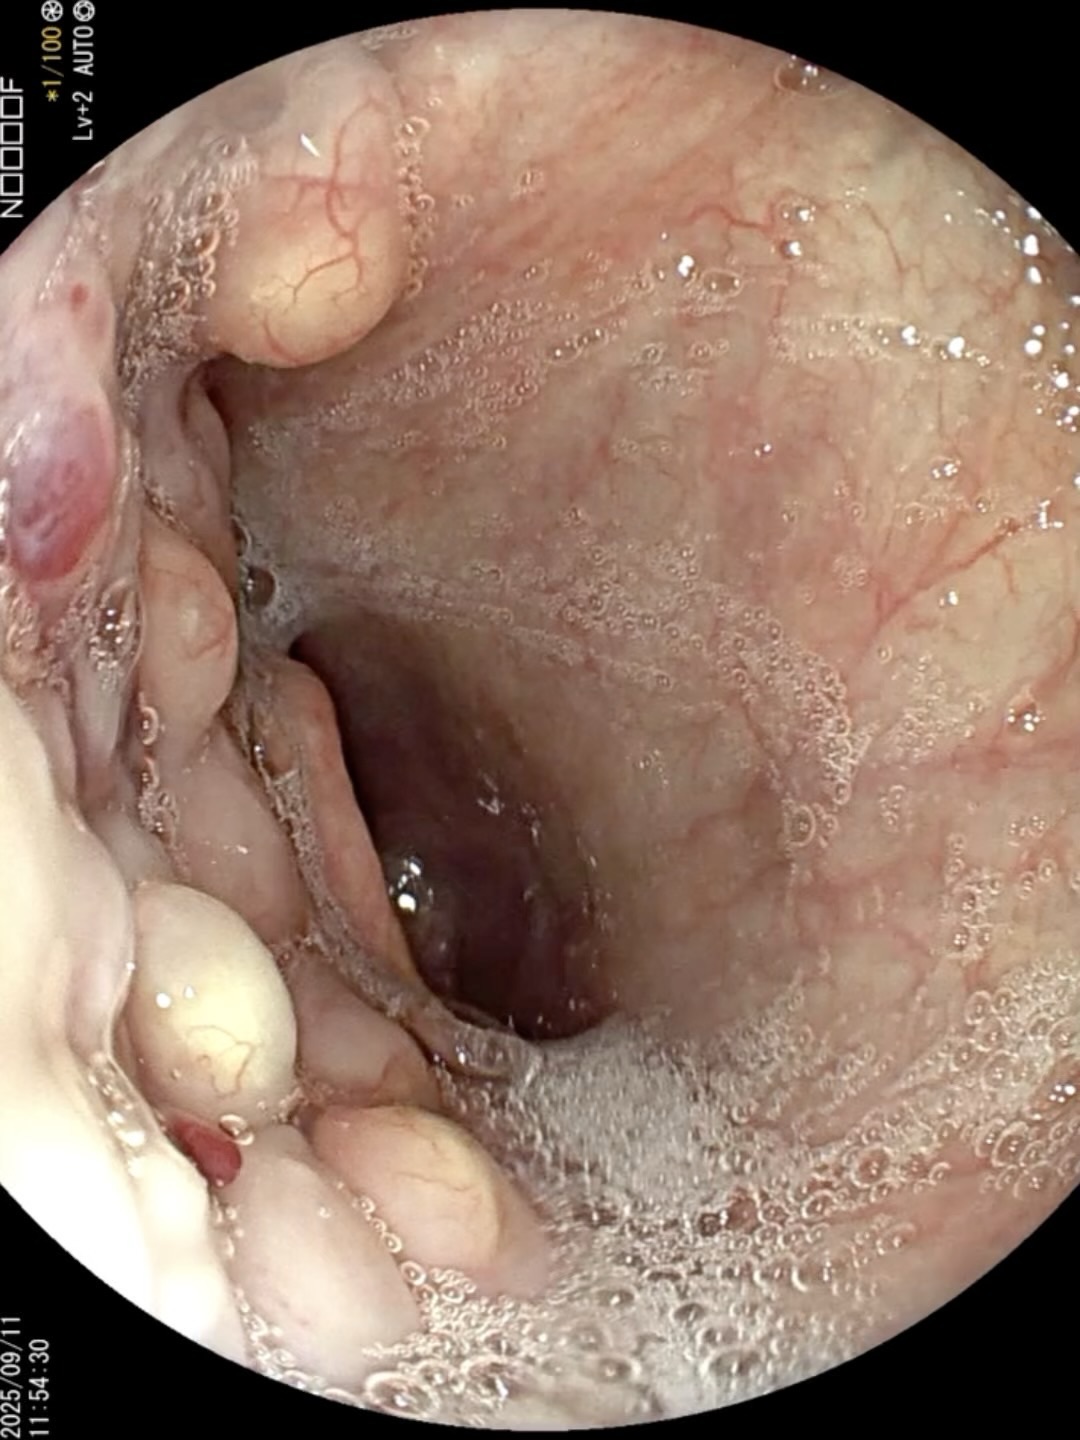

病例胃瘘口-经胃镜下诊断与治疗

患者 老年 男性,腹痛入院。

胃镜诊治如下:

胃瘘 (5)